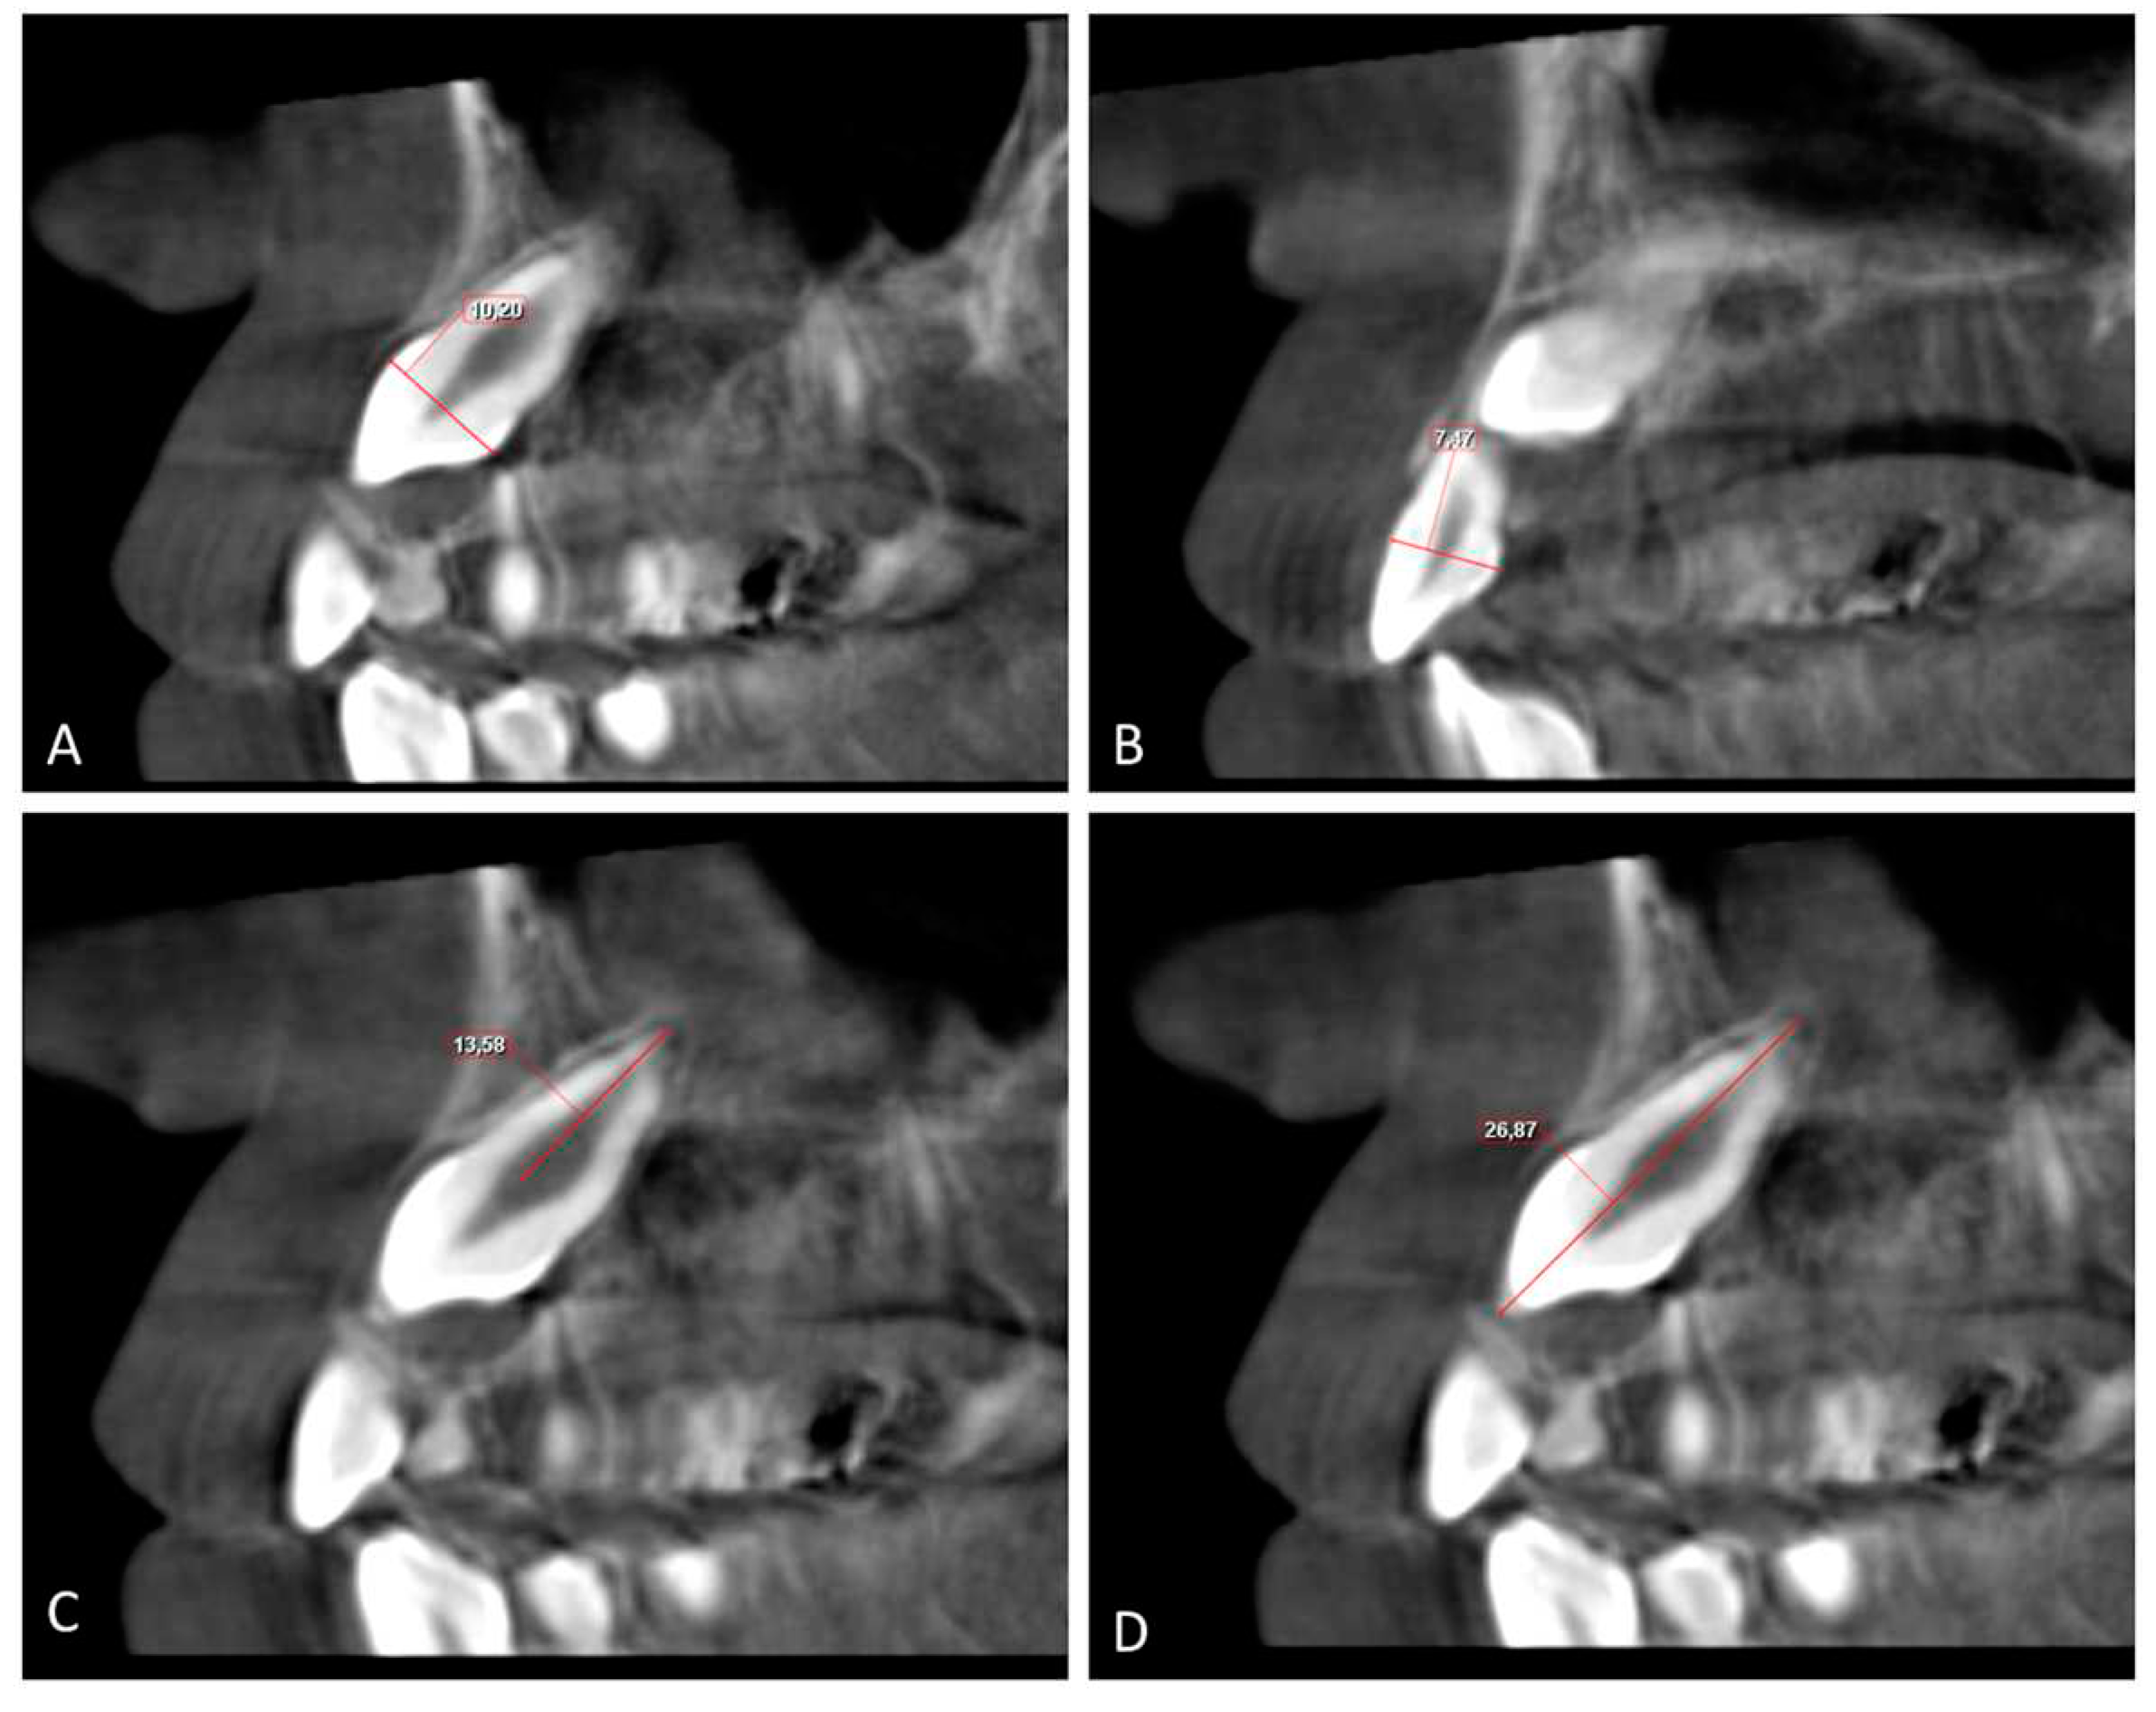

The buccolingual (BL) and mesiodistal (MD) widths of the crowns of the lateral incisor (U2) and canine (U3) were measured from the widest point of the crown perpendicular to the long axis on the sagittal and coronal sections, respectively (Figure 4 and Figure 5).

Root length (RL) was measured from the lowest level of the buccal cementoenamel junction (CEJ) to the root apex, and the total length (L) of the lateral incisor was measured from the incisal tip to the root apex on the sagittal section (Figure 5). The horizontal distance of the maxillary impacted canine (U3 HD) from the tip of the canine cusp to the midline was measured in the axial section. The vertical distance of the maxillary impacted canine (U3 VD) from the tip of the canine cusp to the occlusion plane was measured in the sagittal plane (Figure 4, Figure 5 and Figure 6).

Figure 5. A. Buccolingual width of the canine crown (U3 BL) and B. Buccolingual width of lateral crown (U2 BL); the distance between widest points of the crown on the sagittal section; C. Length of the root canine (U3 RL) and length of the root lateral incisor (U2 RL); the length from lowest buccal CEJ level to the root apex on the sagittal section. D. Total length of the canine (U3 L) and total length of the lateral incisor (U2 L); the length from the incisal tip to the root apex on the sagittal section. CEJ: Cementoenamel junction.